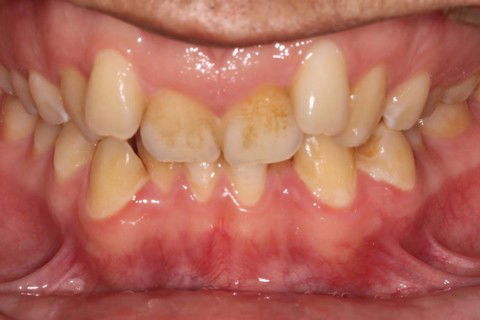

Inicial Frontal

Paciente: Sexo masculino, 16 anos

Queixa principal: Apinhamento

Diagnóstico: Classe II, divisão 2

Sugestão de Tratamento: Tratamento ortodôntico com o uso do sistema de alinhadores removíveis Invisalign. Sem extrações dentarias, pois o perfil do paciente não era favorável. Por ser um paciente jovem, optou-se por uma expansão dentária controlada, buscando a remodelamento dos arcos.